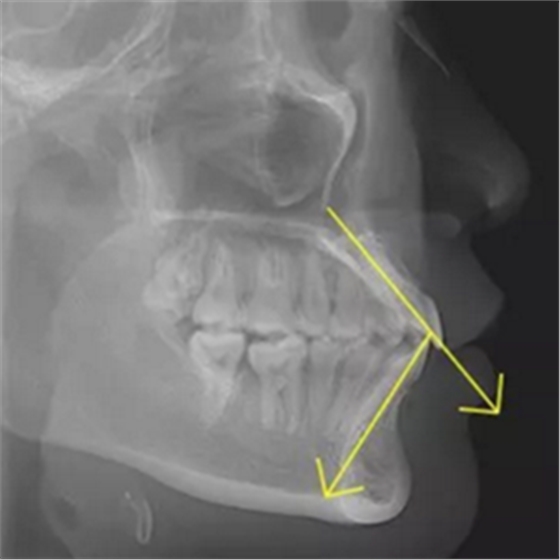

但前牙閉鎖合是上前牙下垂伸長,內(nèi)扣完全鎖住了下切牙,正面觀時我們??床坏较虑醒?,下切牙則常擁擠伸長咬到了上腭內(nèi)的牙齦上,上下前牙發(fā)生的交角幾近180°。

前牙閉鎖合交角